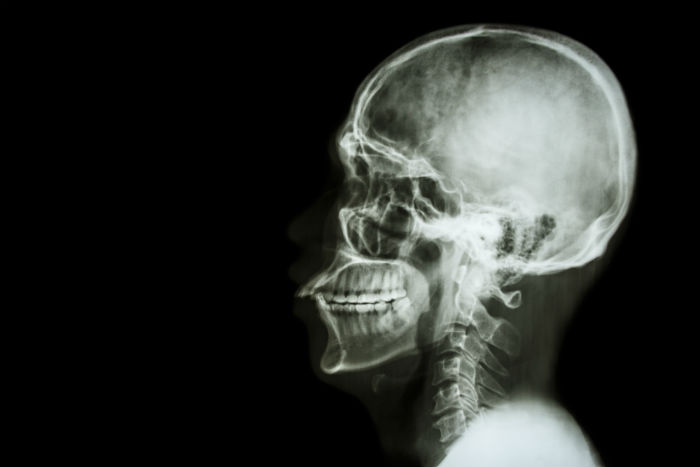

A inicios de este mes, Sergio Canavero publicó el protocolo de la operación en la revista Surgical Neurology International, la cual consiste en primera instancia en enfriar la cabeza del receptor y el cuerpo del donante para extender el tiempo que las células puedan sobrevivir sin oxígeno. Luego el tejido alrededor del cuello se diseca y los principales vasos sanguíneos se unen mediante pequeños tubos, antes de cortar la médula espinal de cada persona, explican en New Scientist.

Una vez que la cabeza es trasladada al nuevo cuerpo, el médico piensa usar un químico llamado Polietilenglicol para poder fusionar ambos extremos de la médula e inyectar el cuerpo con esta sustancia durante las siguientes horas.

Posteriormente los músculos son suturados y el paciente se mantiene en coma durante las siguientes tres o cuatro semanas para que no pueda moverse. Cuando despierte, según el médico,podrá mover y sentir su cara, así como hablar con la misma voz. Con ayuda de fisioterapia, será capaz de caminar en un año.